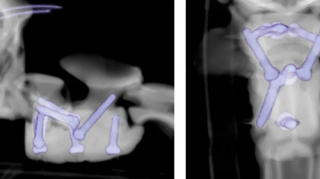

Le travail des vétérinaires a duré 5 heures et a été un franc succès. Pour soigner Arthur, les chirurgiens ont stabilisé sa colonne vertébrale avec des vis spéciales imprimées en 3D et du ciment chirurgical.

Le chirurgien vétérinaire principal, Rocio Orlandi, est revenu sur les équipements mobilisés durant l’opération : « L'utilisation de la technologie d'impression 3D améliore la précision de cette chirurgie complexe. »